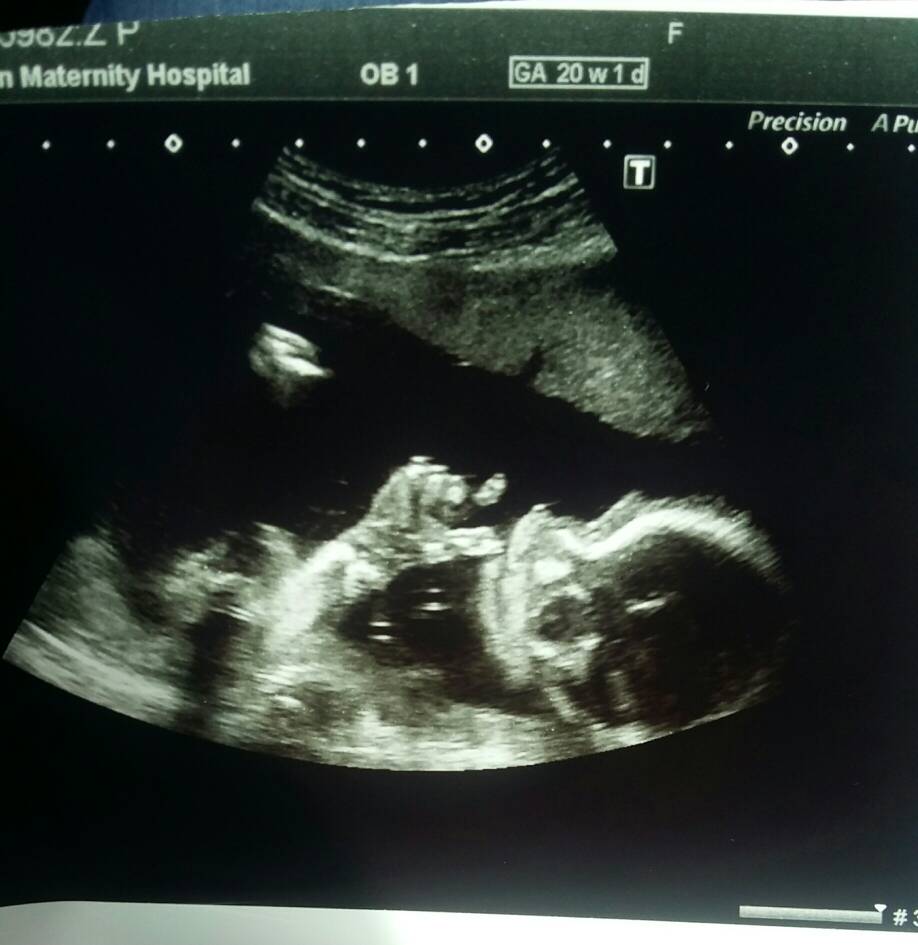

Mała gimnastyczka rośnieNasza wygimnastykowana córeczka [emoji4]Zobacz załącznik 869652Zobacz załącznik 869653